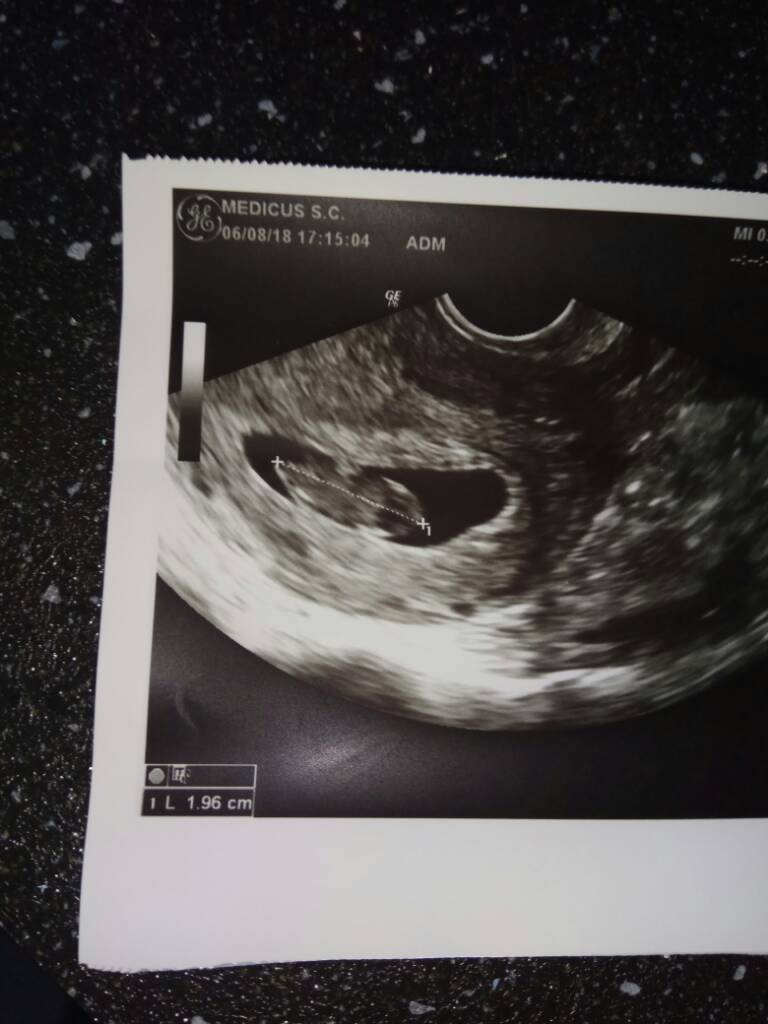

A oto zdjęcie maleństwa z wczorajszej wizyty[emoji7]

IMG_20180807_053411.jpg

• IMG_20180807_053411.jpg

62 KB · Wyświetleń: 455